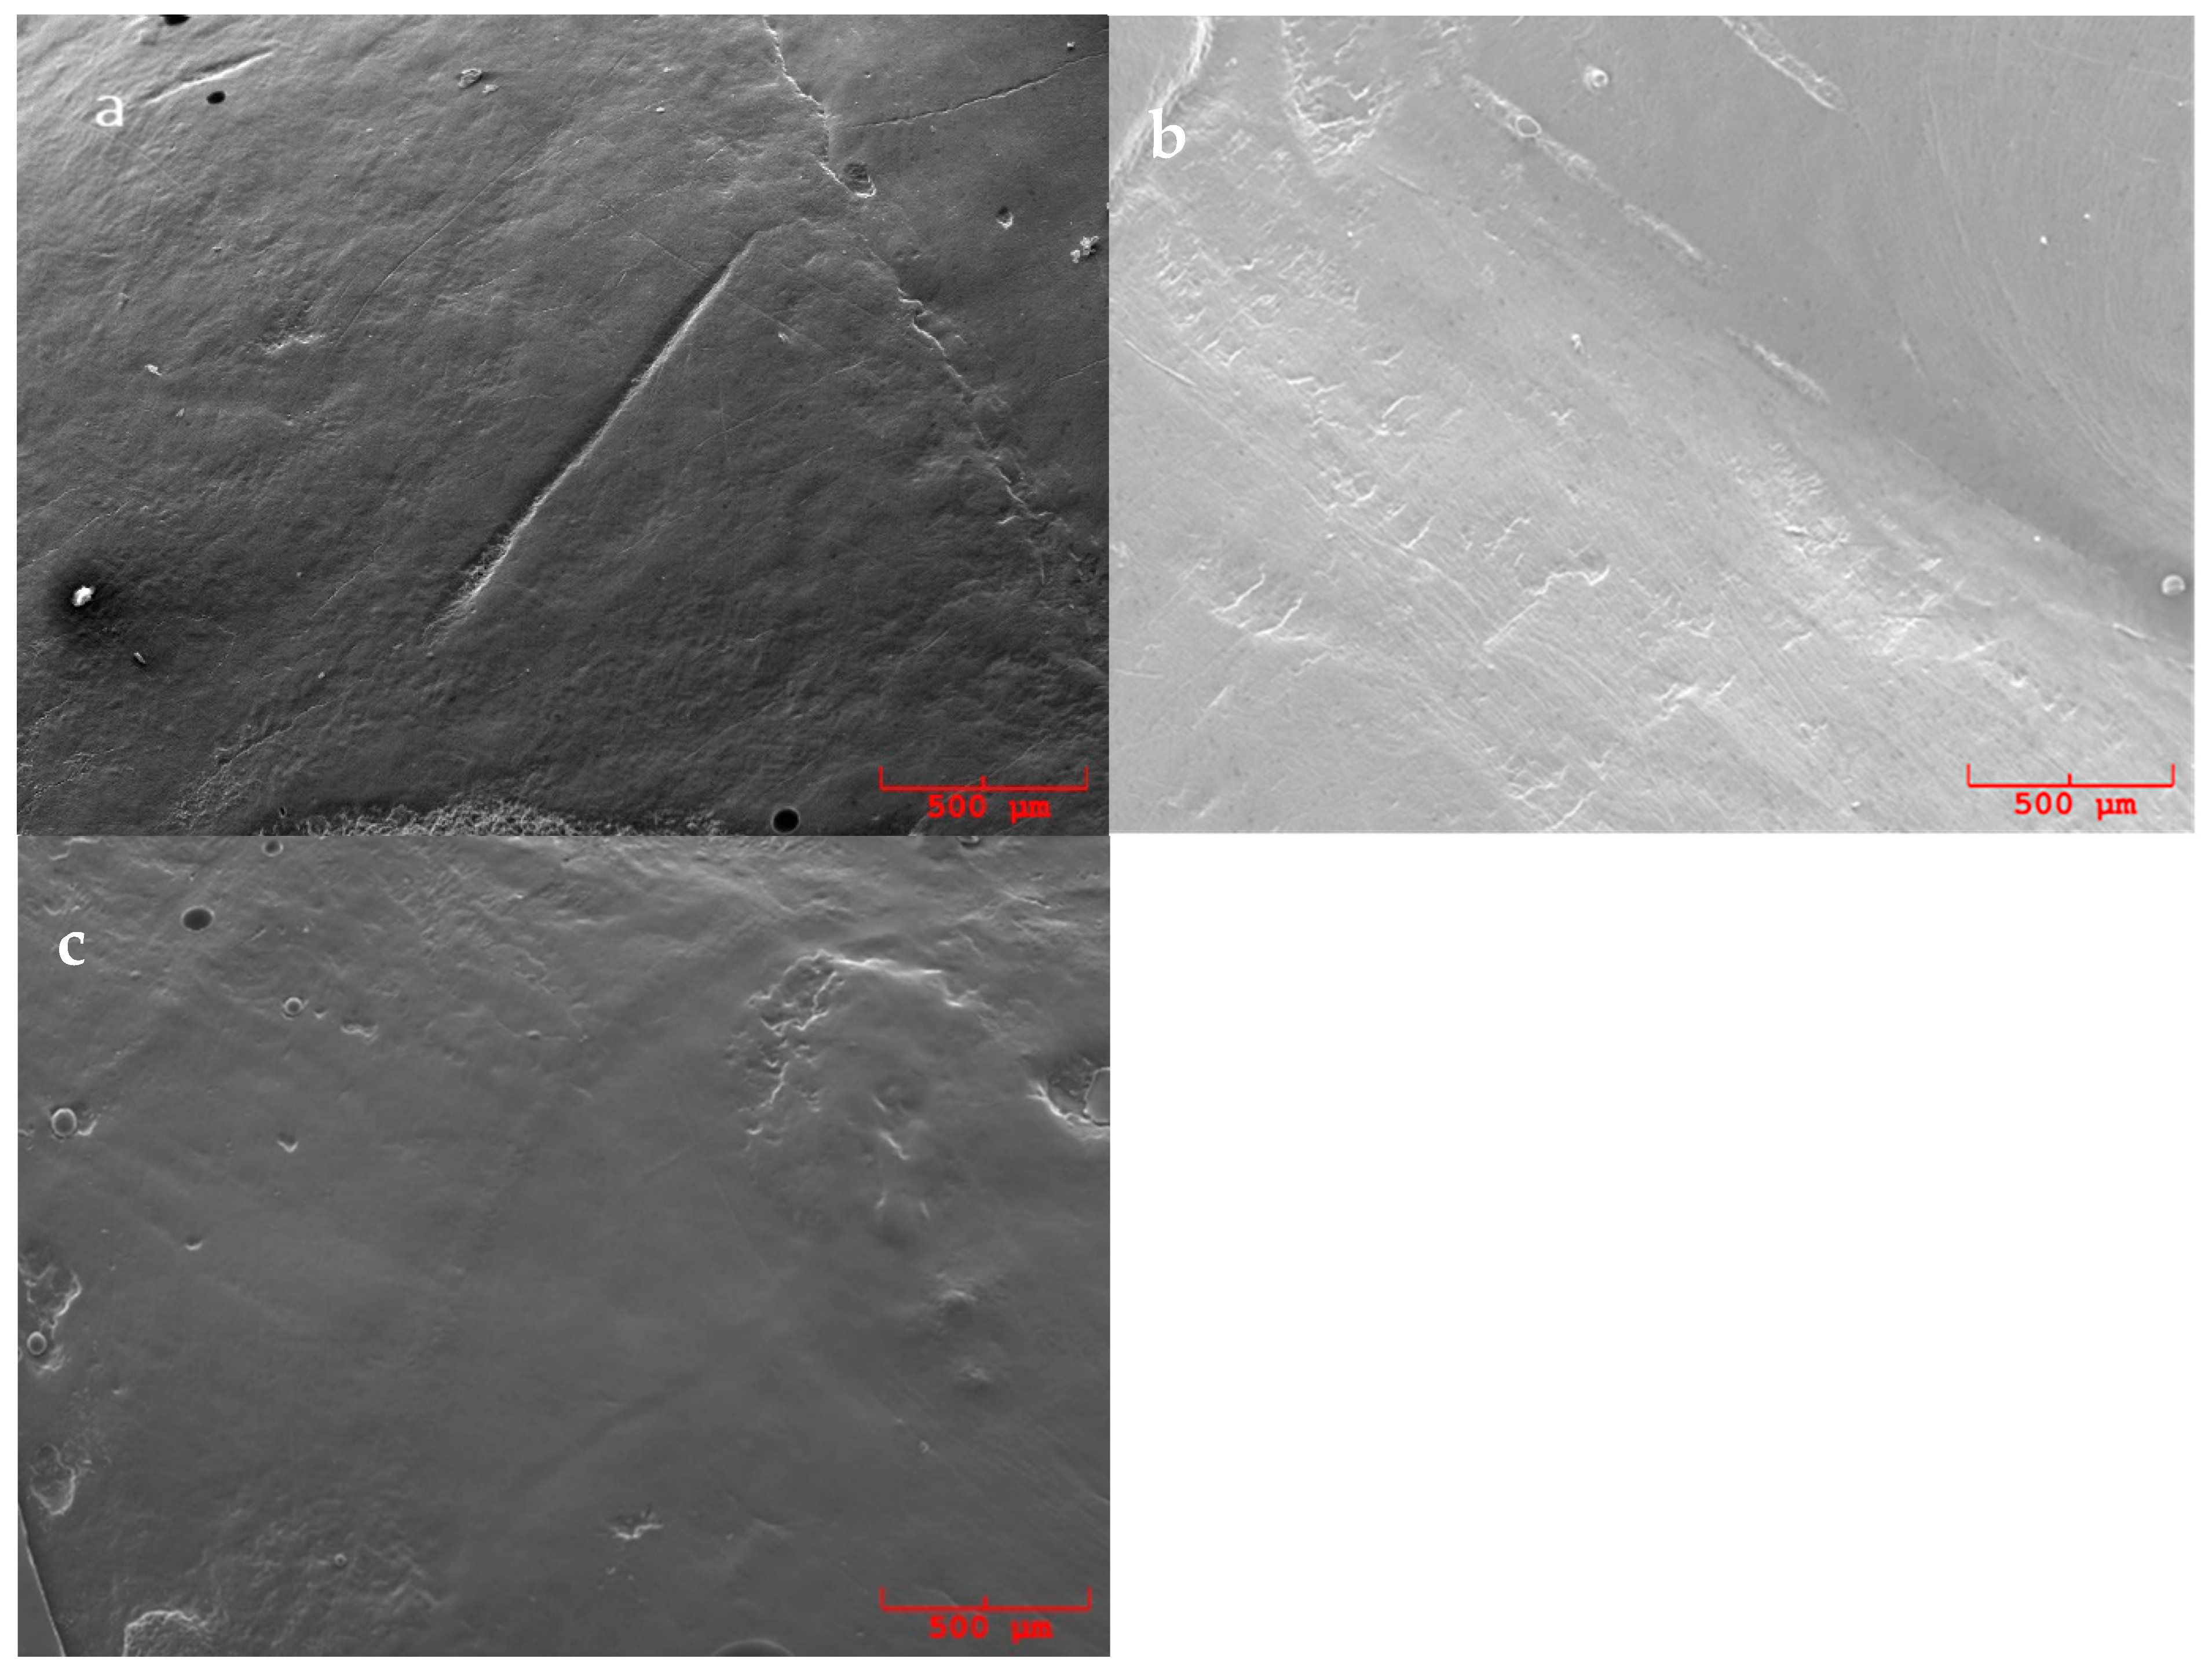

3.2. SEM Evaluation

- 0.

- Regular root surface, without loss of substance and signs of instrumentation;

- 1.

- Regular root surface with isolated instrumentation marks;

- 2.

- Widespread presence of signs produced by the instrumentation;

- 3.

- Irregular surface and/or presence of lesions produced by the instrumentation.